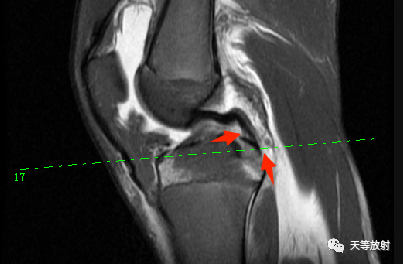

上图:双后交叉韧带征。提示外侧半月板桶柄状撕裂。

上图:横断位如箭头所指示。